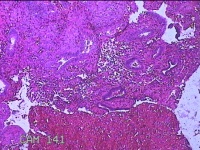

宫腔内组织

性别

女

年龄

46岁

临床诊断

异常子宫出血

一般病史

阴道流血伴血块6天。

标本名称

大体所见

灰白暗红色不规则碎组织2.5x2x0.7cm一堆。